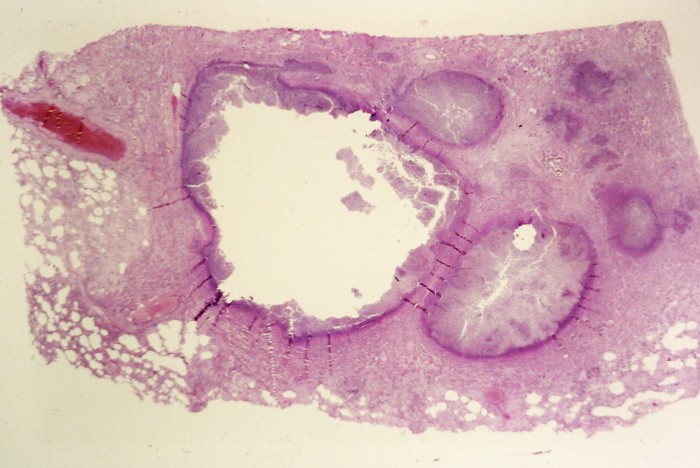

Abscess